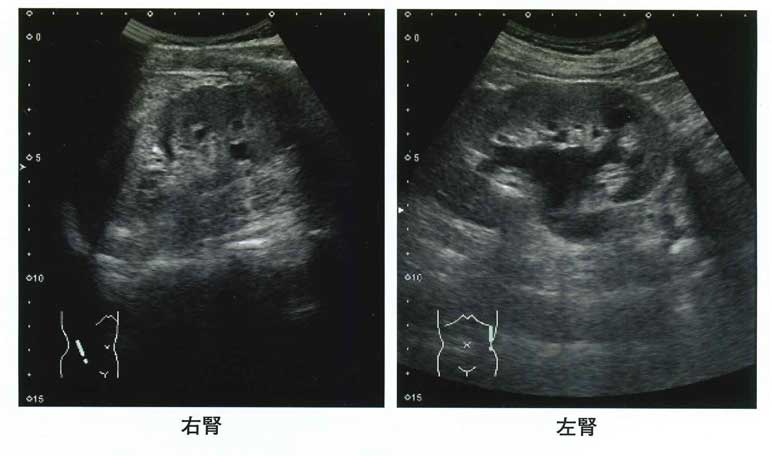

答え:b 尿閉

「尿量の減少を主訴に来院にした。」

「約1年前から排尿困難を自覚していたが医療機関を受診しなかった。」

「昨夜、飲酒をした後から排尿困難感が悪化し、尿が間欠的に少量しか出なくなった。」